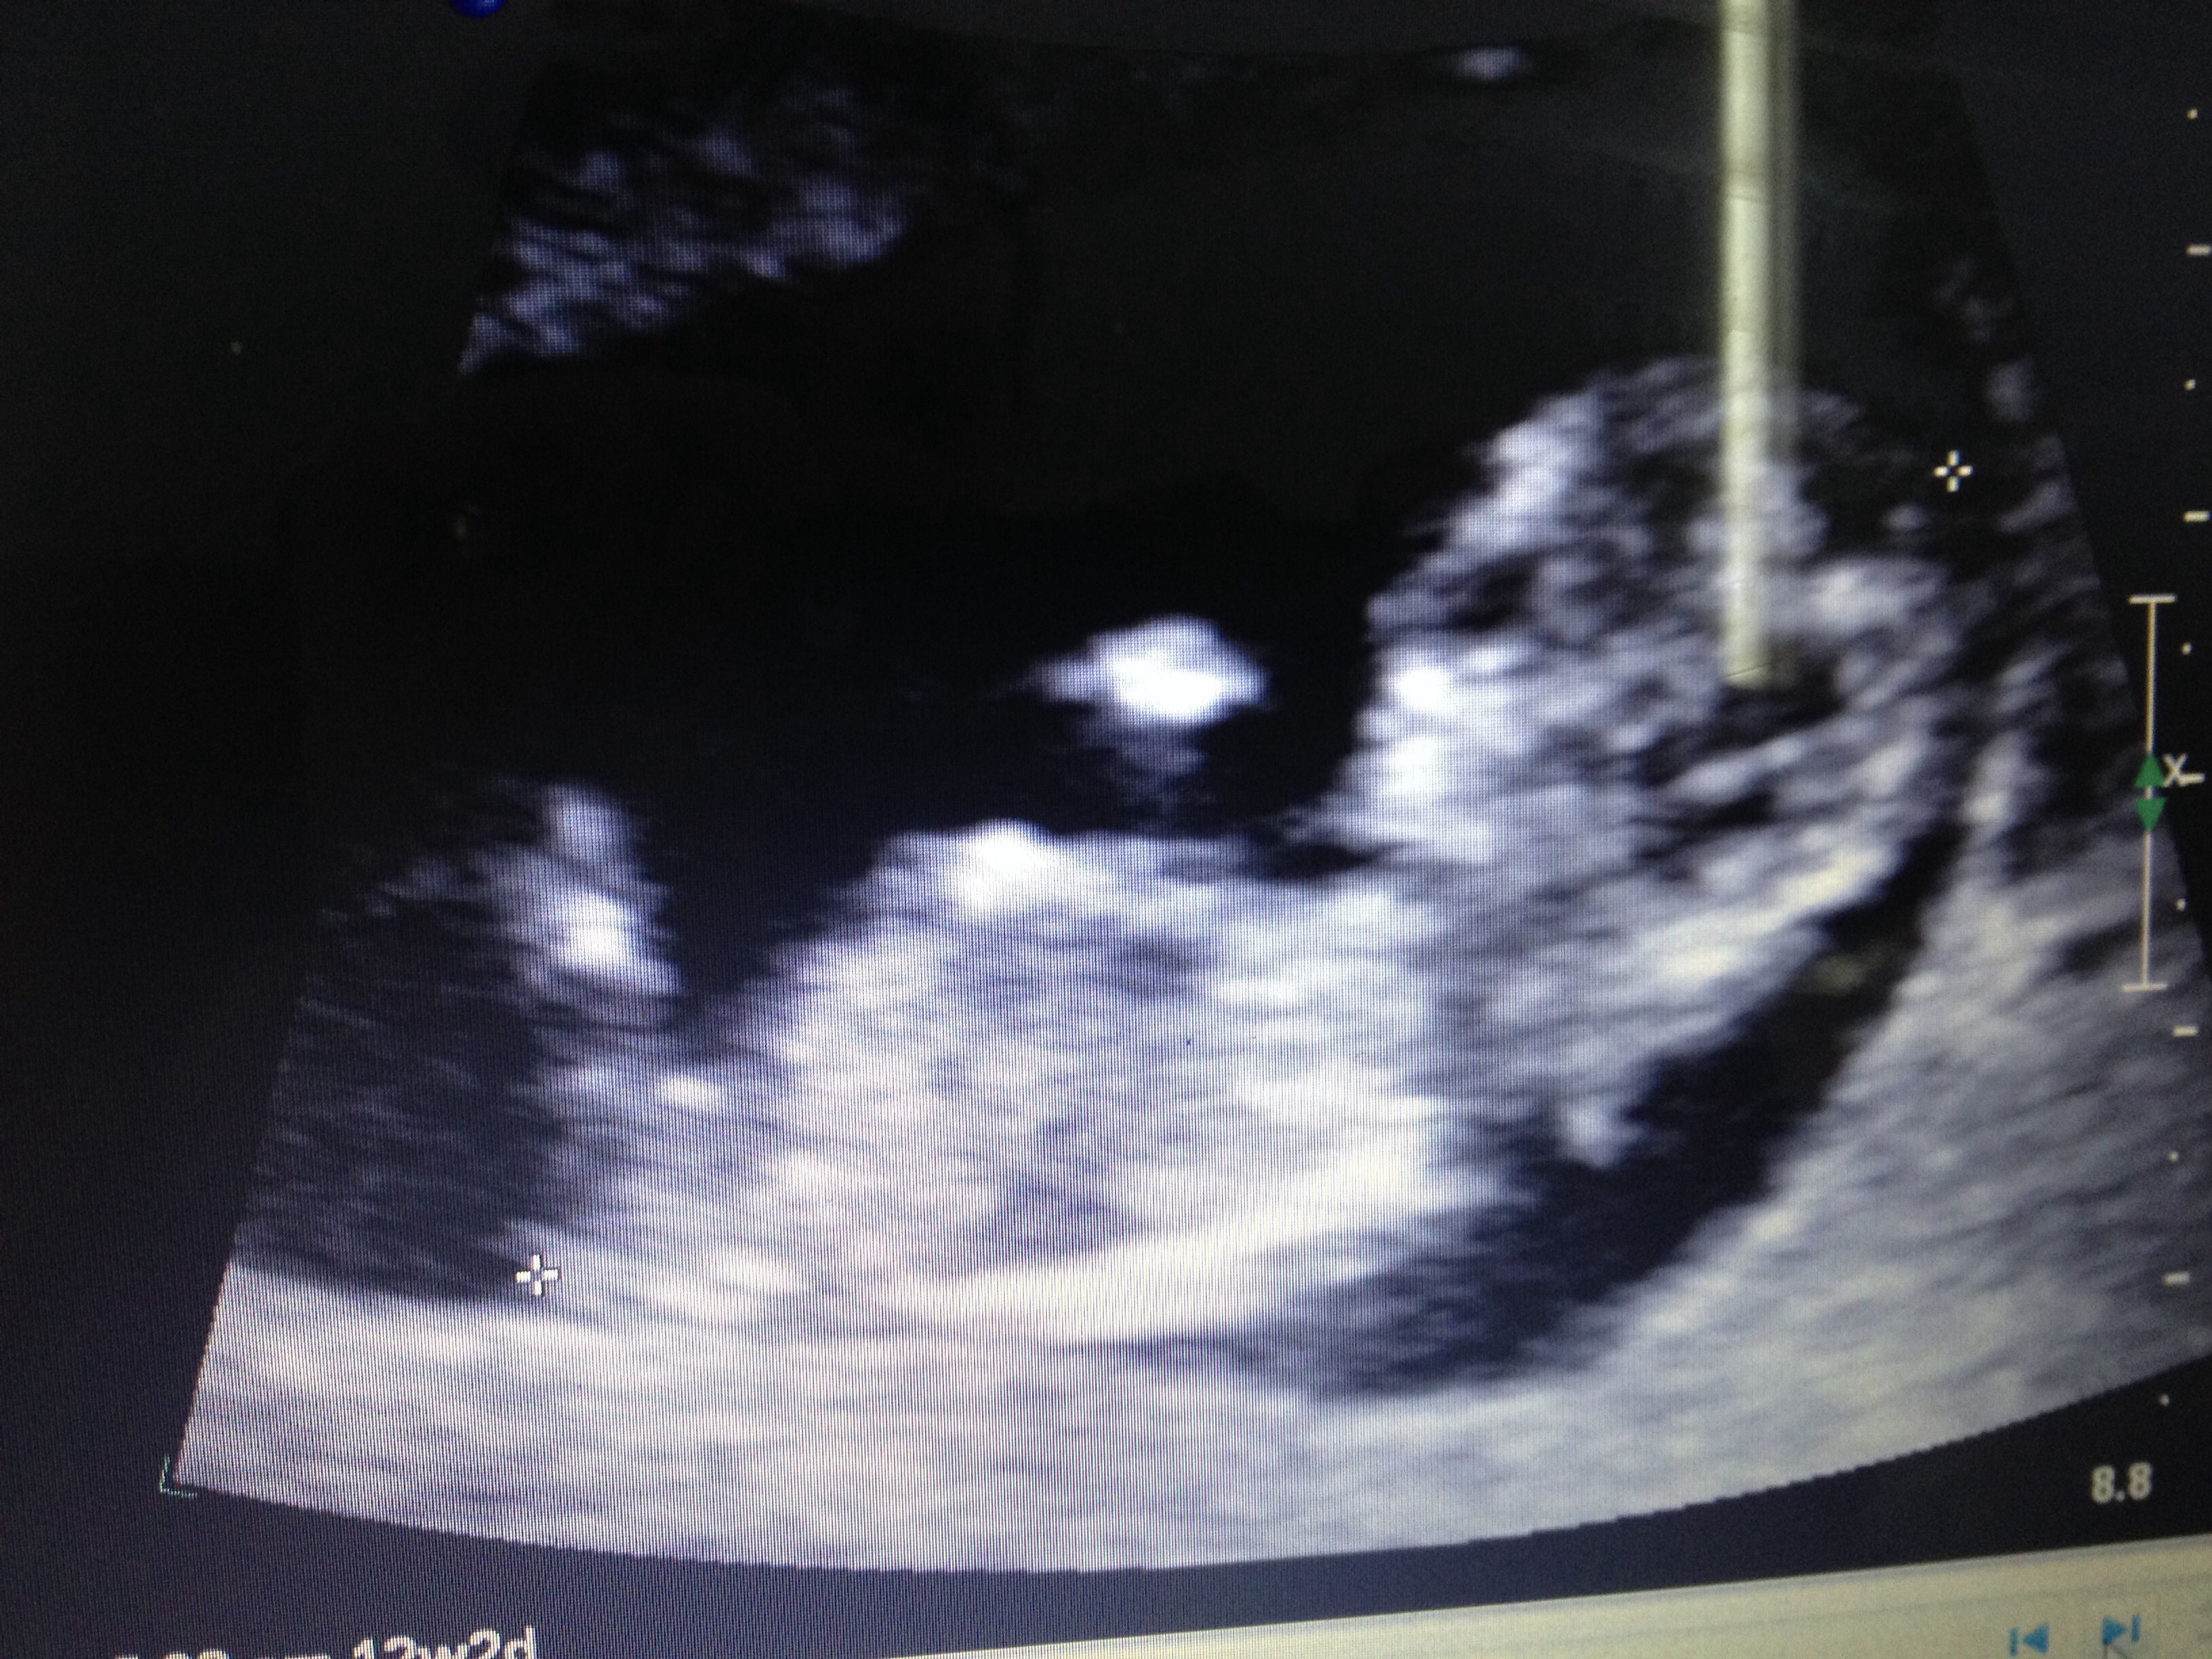

Please help me guess from this nub shot. One more sleep and I find out!!!Attachment 20943

12w 2days

Girlie nub to me x

I guess girl.

Confirmed boy at 19 weeks, off to the gender disappointment forum I go!